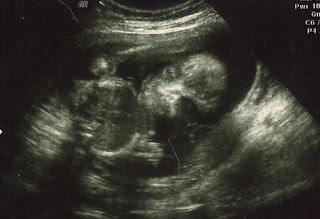

A shot of her face! For a brief second I saw a shadow of her mouth and I think her and Sophie are going to have the same mouths. Klint and I can't decide whose mouth it is, but we are leaning more towards mine.

We confirmed that she is a little girl! She is measuring a day ahead, but her weight was a day behind. So, I am saying she is right where she needs to be. I tried to get the technician to predict how much she would weigh when she was born and she wouldn't. I looked at the growth chart and predicted that if she keeps going like she is she will be around the same weight as Sophie. The technician said that I can expect her to be a little bigger....we'll see!

I little hand to the side! Can't wait to meet our little girl!